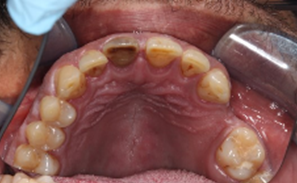

UL6 Internal inflammatory resorption perforating palatal root. Repaired with MTA.

12 month review (crown carried out by GDP)